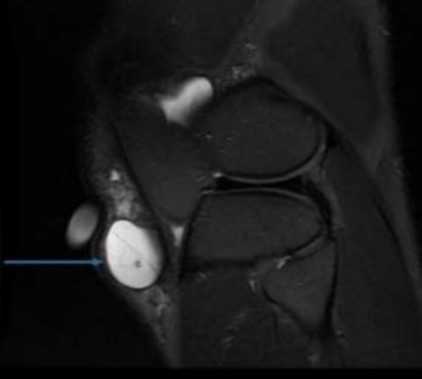

Киста Бейкера - осложнение бурсита подколенной сумки на МРТ

Хронический процесс часто является следствием неадекватного лечения острого воспаления. Заболевание развивается на фоне постоянной вибрации или механического воздействия на сустав.

Длительно существующую патологию отличает латентное или медленно прогрессирующее течение, с периодическими эпизодами обострения. Хроническое воспаление бурсы приводит к значительному накоплению экссудативной жидкости в полости синовиальной сумки, что способствует формированию кистозных образований. Магнитно-резонансную томографию проводят в рамках предоперационного исследования.

Бурсит медиальной коллатеральной связки коленного сустава на МРТ (стрелка)

Магнитно-резонансное сканирование показывает точную локализацию и размеры воспалительного процесса. В зависимости от местоположения пораженной синовиальной сумки чаще выделяют: супра-, пре-, инфрапателлярный бурситы.